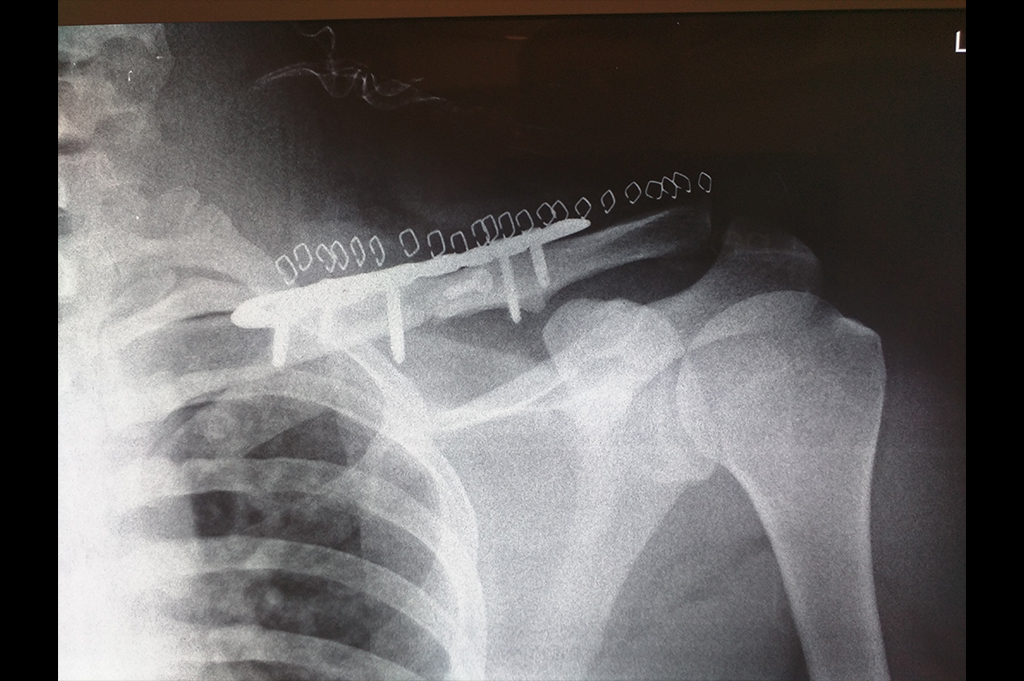

Clavicle